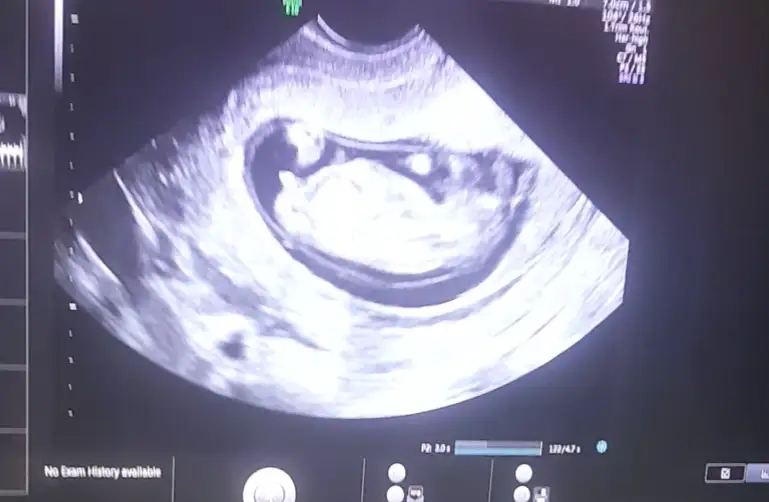

Net değilKizlar kim yorumluyor burda nub teorisini..Ben 18.hafta icindeyim gerci ama hala ogrenemedim cinsiyetini beninkinede bakarmisiniz bu da eksik kalmasınburda 12+2 gunluk videoda cektim goruntuyu tam bu bolge sanirim baktiginiz

Nubu ne dik nede paralel tam karşıya bakıyor nubu böyle usgler yanıtıyor beni başka usg varmı nubu erkek desem erkek gib tam dik değilBen de yorum istiyoruuum12+2 burdaEki Görüntüle 2633538

Çok küçük çıkinti var . Erkek gibi sanki diyecem emin olamıyorum 13-14 haftada tekrar paylaşınCanım videodan aldığım bir foto daha paylaşayım ☺Eki Görüntüle 2633626

Sanki kız gibi emin olamıyorum çok net değil beyaz usg başka varsa paylaşın 11 12 de olabilirEki Görüntüle 2633651 13 haftalık nub bakarmısınz rica etsem